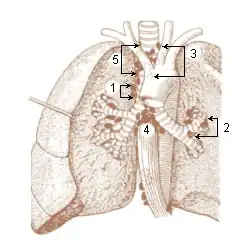

1. Pulmonary juxtaesophageal 2. Bronchopulmonary (hilar) 3. Superior tracheobronchial 4. Inferior tracheobronchial 5. Paratracheal | |

These lymph nodes form four main groups including paratracheal, tracheobronchial, bronchopulmonary and pulmonary nodes.

- Paratracheal nodes are located on either side of the trachea.

- Tracheobronchial nodes can be divided into three nodes including left and right superior tracheobronchial nodes, and the inferior trachiobronchial node. The two superior tracheobronchial nodes are located on either side of trachea just before its bifurcation. The inferior tracheobronchial node is located just below the bifurcation in the angle between the two bronchi.

- Bronchopulmonary nodes (hilar nodes) situate in the hilum of each lung.

- Pulmonary nodes are embedded the lung substance on the larger branches of the bronchi.